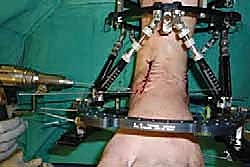

خطوات جراحة تثبيت مفصل الكاحل الأمامي بالتفصيل (Step-by-Step Surgical Procedure)

1. الوضعية والشق الجراحي (Positioning and Incision)

يستلقي المريض على ظهره (Supine position). يتم استخدام عاصبة (Tourniquet) حول الفخذ لتقليل النزيف وتوفير رؤية واضحة. يقوم الدكتور هطيف بإجراء شق طولي أمامي فوق مفصل الكاحل، عادة بين وتر العضلة الظنبوبية الأمامية (Tibialis Anterior) ووتر العضلة الباسطة الطويلة لإصبع القدم